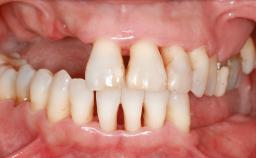

A 20-year-old woman was referred for implant therapy in 2004. Her medical history revealed no significant findings, and neither did she smoke nor take any medications. An extraoral examination revealed no abnormalities of the skin, hair or nails. The intraoral examination revealed only 11 permanent teeth clinically. These were normal in shape, size, and color. In addition, eight retained deciduous teeth (53, 62, 63, 71, 72, 73, 81, 82) were present. No abnormalities were detected during the general examination. The family history revealed that the patient’s father and two sisters were on record with similar conditions. The clinical examination revealed a thick gingival biotype. No recession of the attached gingiva was noted, but the retained deciduous teeth were mobile and unsightly. As a syndrome had not been diagnosed, the case was categorized as non-syndromic oligodontia.

Width of Edentulous Span 1 tooth (>= 7 mm) 1 tooth (< 7 mm) 2 teeth or more

Bone Volume Horizontally and vertically sufficient Horizontally deficient Deficient vertically or deficient vertically AND horizontally

Defining Characteristics Up to three missing teeth to be replaced with an implant-borne restoration or restorations